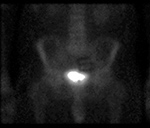

Figure 33 |

60 year-old man with history of lung cancer and left hip arthroplasty suffered from stiffness in the left hip region. Axial CT, FDG PET, fused axial, and coronal PET-CT demonstrates increased uptake of FDG in heterotopic ossification in the musculature of the left thigh. |